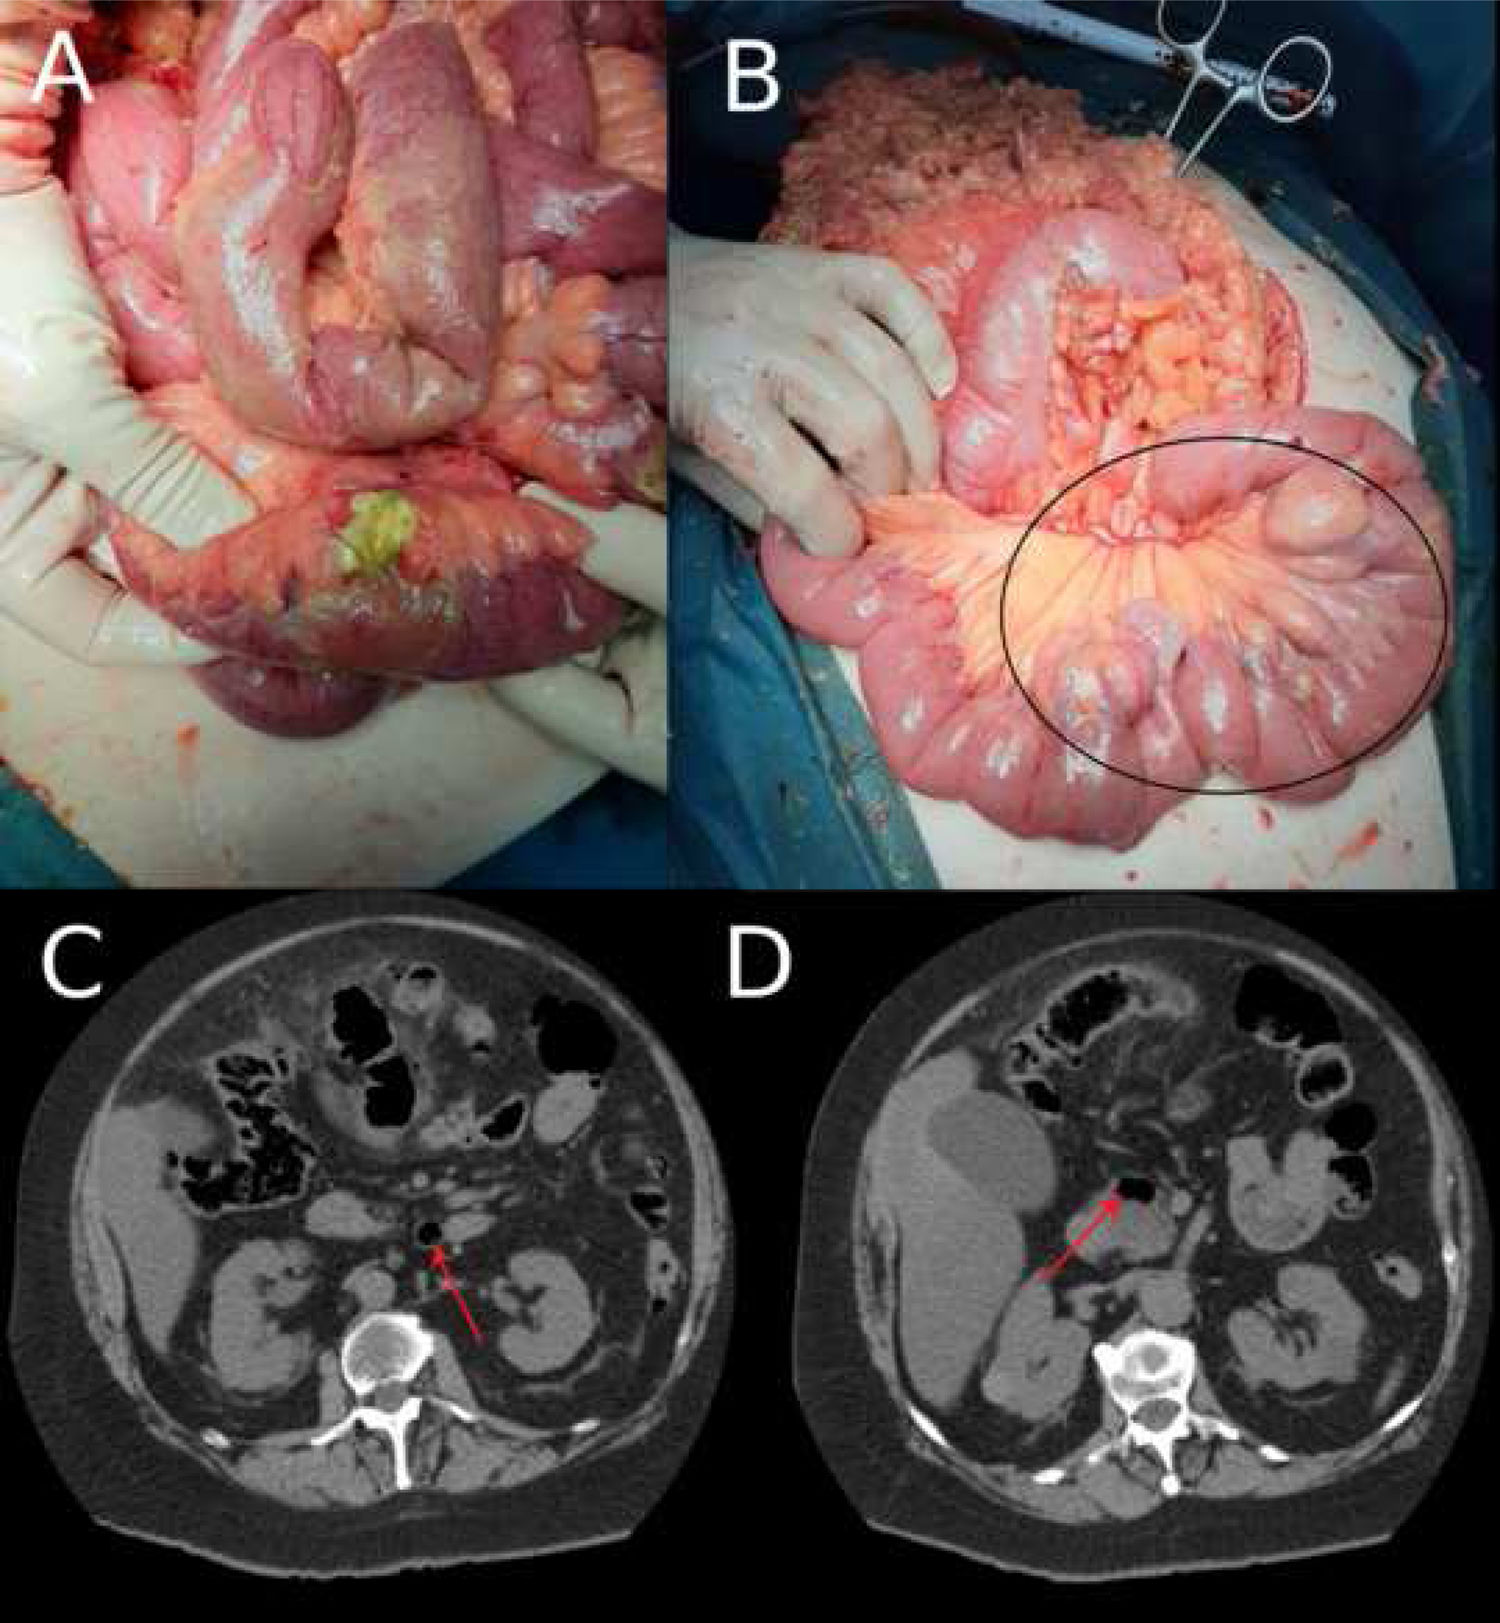

1A) Imagen intraoperatoria: perforación de un divertículo yeyunal distalgrande único. 1B) Imagen intraoperatoria: múltiples divertículos yeyunales grandes, en el borde mesentérico, desde practicamente el ángulo de Treitz hasta 80 cm del mismo (círculo negro). 1C y 1D) Imagen del CT abdominopélvico; vista axial. La imagen muestra los divertículos yeyunales (flechas rojas).

Mujer de 66 años que acude a Urgencias por dolor abdominal de tipo cólico en la región epigástrica de cuatro días de evolución, con náuseas y vómitos asociados. Presentaba fiebre de 38°C y en la exploración física el abdomen era blando y depresible, doloroso a la palpación de manera difusa. El signo de Blumberg fue positivo. La analítica mostraba leucocitosis (15,9 × 109/L) y la PCR estaba elevada (3,3 mg/dL). Se realizó un CT abdominopélvico, en el que se observó neumoperitoneo, líquido libre intrapélvico y aumento de la densidad de la grasa mesentérica en hemiabdomen izquierdo. Se evidenció también diverticulosis a nivel del sigma. El diagnóstico inicial de la paciente fue de una diverticulitis sigmoidea perforada, por lo que se decidió realizar tratamiento quirúrgico urgente. Intraoperatoriamente se observó una peritonitis diseminada en todos los cuadrantes con colecciones interasas y múltiples divertículos yeyunales (10 divertículos distribuidos en el yeyuno, que comenzaban desde inmediatamente distal al ángulo de Treitz), con una gran perforación de un divertículo en borde mesentérico yeyunal a 80 cm del Treitz (fig. 1). Se resecó el fragmento yeyunal con el divertículo perforado, realizando una anastomosis T-T mecánica. El postoperatorio transcurrió sin incidencias y la paciente fue dada de alta al séptimo día del postoperatorio. Revisando el CT tras la cirugía, se podían identificar los divertículos (fig. 2). Posteriormente, el estudio anatomopatológico confirmó la enfermedad diverticular yeyunal con perforación, así como una marcada inflamación del mesenterio intestinal.